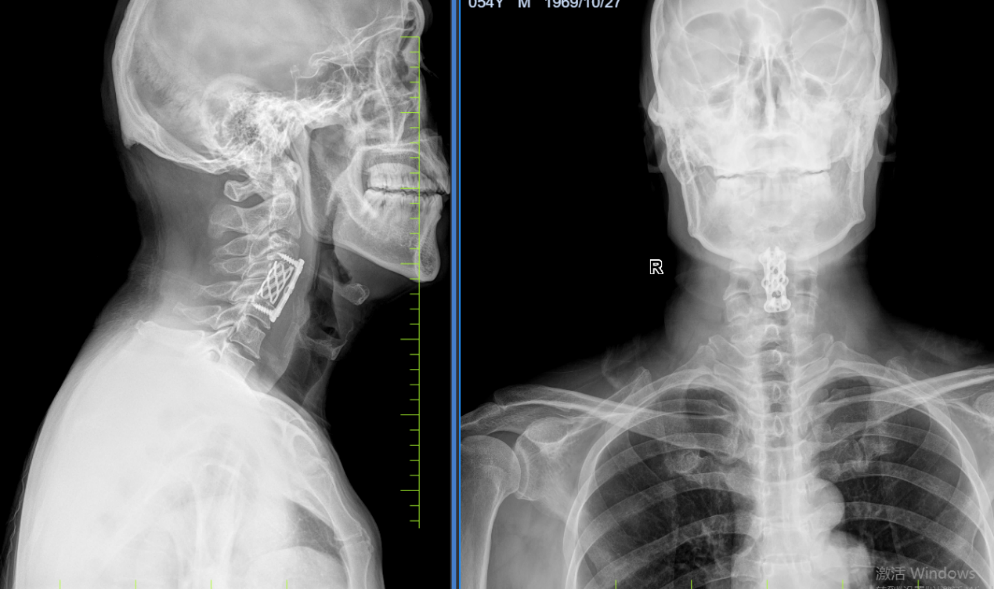

病例八:患者,男,54岁,因“颈肩部酸痛不适半年,伴左下肢行走不稳2月余”入院。诊断:脊髓型颈椎病;行颈4椎体次全切+椎管减压融合内固定术(ACCF)。手术顺利,术后进行康复训练中,功能恢复良好。

脊髓型颈椎病 术前磁共振

脊髓型颈椎病 术后X线